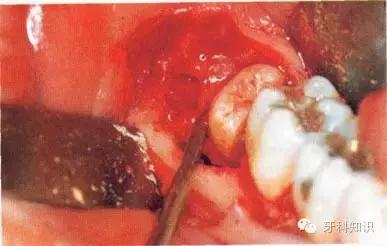

a第Ⅱ类,b分类中位阻生。左下颌第三磨牙阻生,位于黏膜下。磨牙后区切开后,作近中切口,使用12号刀片沿牙龈扇贝状外形切透龈沟至牙槽嵴顶,避免将龈乳头切除。图中近中切口延长至第二前磨牙,便于翻瓣,更好地显露磨牙后区的骨质

b翻瓣后,阻生牙的(牙合)面位于第二磨牙颈部及其牙槽嵴顶均清晰可见。切割牙体前先去除舌侧骨板以保护软组织